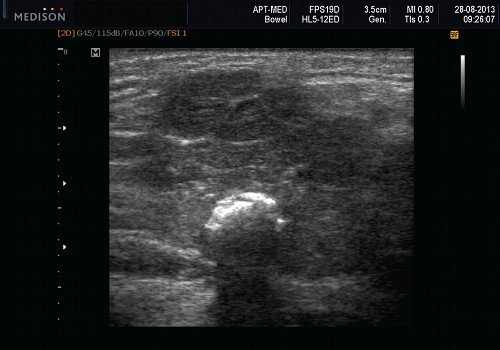

Рис. 6. Камень в паренхиме поднижнечелюстной слюнной железы.